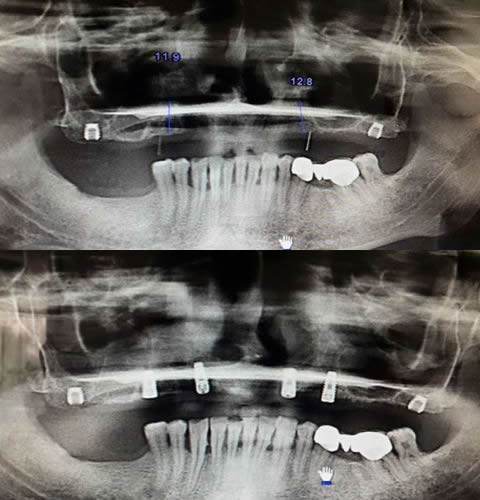

Diş implantı eksik olan diş veya dişlerin yerine yerleştirilen titanyumdan yapılmış yapay bir diş köküdür.